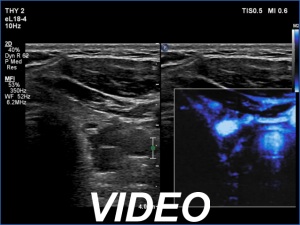

Ultrasonography. The thyroid was echonormal. There was a hypoechoic mass dorsal and under to the lower pole of the left thyroid lobe.

We tried to gain cytological material two-times from the mass but it was doubtful whether we reached the hypoechoic mass. Aspiration cytology was non-diagnostic. Wash-out parathormone was 0.1 pg/ml.